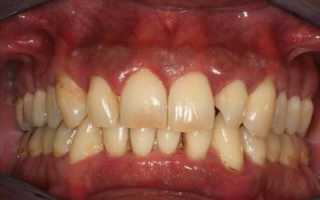

Для течения пародонтита характерны 3 стадии, и симптоматика меняется по мере прогресса заболевания:

- Признаки пародонтита в лёгкой степени совсем незначительны. Дёсны воспалены, в процессе чистки зубов умеренно кровоточат, но без болевых ощущений. Пока не поражена пародонтальная связка, процесс заболевания считается обратимым.

- На средней стадии пародонтита кровоточивость значительно увеличивается, возможны ощущения зуда и жжения. Десна отекает и меняется в контуре, а размер кармана десны доходит до 6 мм.

- Переход в тяжёлую форму пародонтита сопровождается стремительным разрушением костной ткани, зубы теряют опору, веерообразно расходятся и шатаются. На данной стадии заболевания появляется резкий гнилостный запах изо рта, нарушается жевательная функция, и выпадают первые зубы. Глубина кармана десен превышает 6—7 мм.